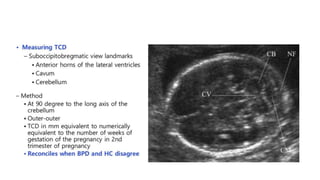

Biparietal diameter

• The BPD is the maximum diameter of a transverse

section of the fetal skull at the level of the parietal

eminences.

• Measured from the outer edge of the proximal skull to

the inner edge of the distal skull at the level of thalami &

cavum septum pellucidum.